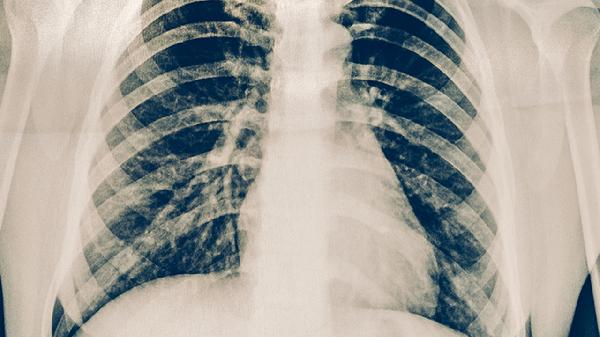

肋骨神经痛是怎么回事?原因你了解吗

肋骨神经痛可能由肋间神经炎、胸椎退行性变化、带状疱疹、外伤或胸椎间盘突出等引起。这种疼痛通常表现为胸部或肋骨之间的刺痛、...